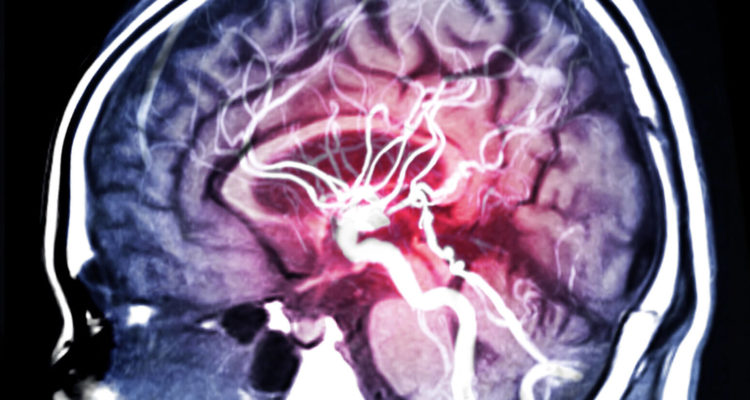

Інсульт: несподіваний продукт, який підвищує ризик

Є способи, якими люди можуть знизити ризик виникнення цієї серцево-судинної події. Двома найбільш ефективними є збалансоване харчування та регулярні фізичні вправи. Одним з основних факторів, який слід враховувати у першому випадку, є контроль споживання солі.

Високе споживання солі є одним із основних факторів ризику високого кров’яного тиску, основної причини інсульту.